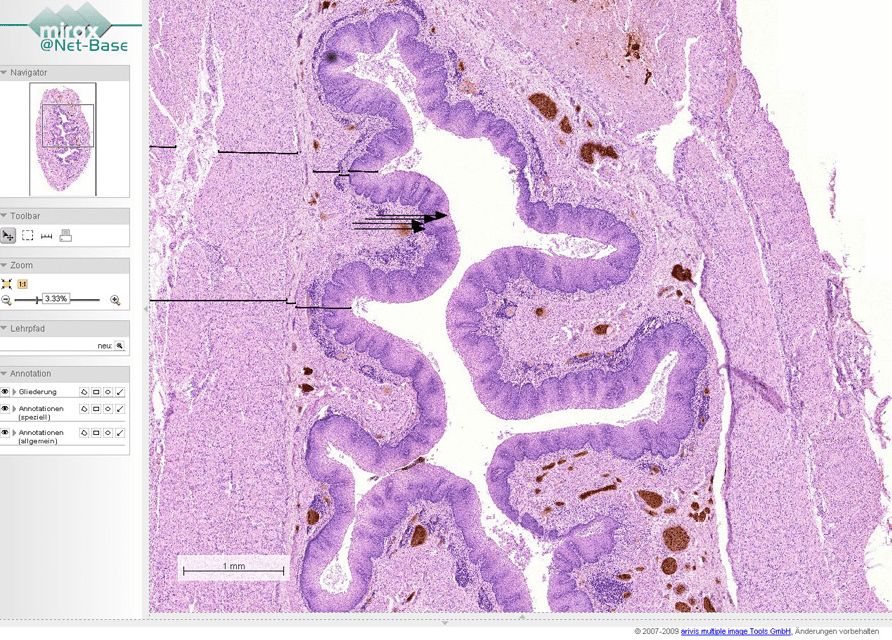

Die Anwendung, auf deren Icon ein kleines Mikroskop abgebildet ist, ermöglicht eine faszinierende Reise durch den menschlichen Körper: Nutzer können ein Präparat, zum Beispiel einen histologischen Schnitt durch den Herzmuskel, auswählen und von der Gesamtansicht ausgehend bis in kleinste Details hineinzoomen. Alle wichtigen Strukturen sind darüber hinaus mit Informationstexten verknüpft.